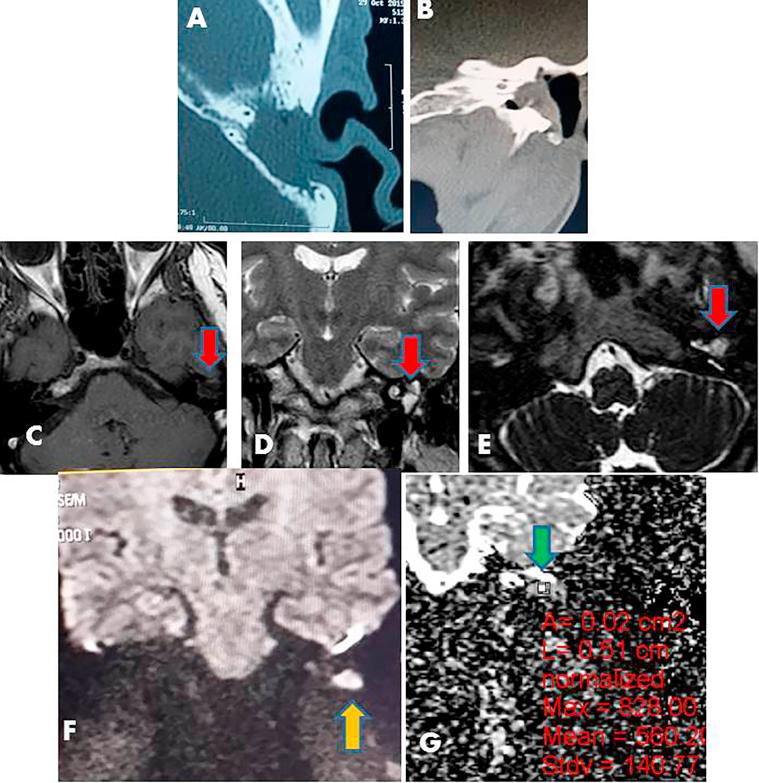

CT showed partial opacification of the tympanomastoid cavity in 10 ears and complete opacification in 21 ears. CT detects 10 cases out of 20 cases of recurrent cholesteatoma with sensitivity 47.6%, specificity 100%, and NPP 47.6%. DWI depicted 21 out of 20 cases proved cholesteatoma patients (sensitivity 100%, specificity 90%, PPV 95.2% and P value is 0.001). All MRI of patients without cholesteatoma were correctly interpreted as showing negative findings for cholesteatoma (specificity = 100%). The ADC of cholesteatoma group (21 ears) were ranged from 553 to 759 × 10 mm/s and the ADCs of non cholesteatoma group (10 ears) was ranged from 1495.8 to 1766.8 × 10 mm/s. Cut off value of cholesteatoma is ≤759 × 10 mm/s.

CT显示鼓室乳突腔部分混浊10耳,完全混浊21耳。CT在20例复发性胆脂瘤中检测出10例,敏感性为47.6%,特异性为100%,阴性预测值为47.6%。DWI在20例经证实的胆脂瘤患者中显示出21例(敏感性100%,特异性90%,阳性预测值95.2%,P值为0.001)。所有无胆脂瘤患者的MRI均被正确解读为胆脂瘤阴性结果(特异性 = 100%)。胆脂瘤组(21耳)的ADC值范围为553至759×10⁻⁶mm²/s,非胆脂瘤组(10耳)的ADC值范围为1495.8至1766.8×10⁻⁶mm²/s。胆脂瘤的截断值为≤759×10⁻⁶mm²/s。